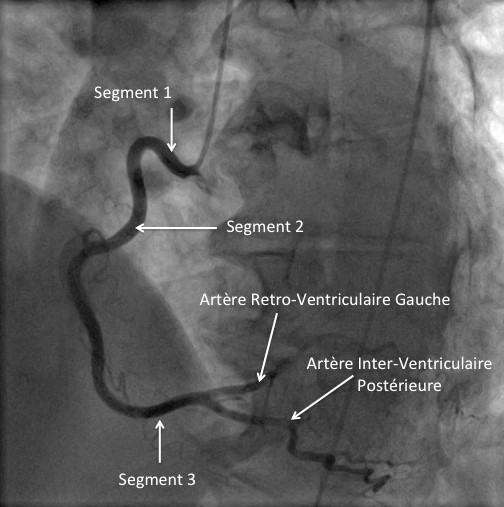

Il est admis que la plaque vulnérable a un cœur lipidique riche avec une chape fibreuse épaisse et se localise le plus souvent au niveau des segments proximaux des principales artères épicardiques.

La plaque à risque de rupture : le prototype de la plaque à risque de rupture contient un large cœur nécrotique très riche en lipide avec une chape fibreuse fine (≤65µm) et inflammatoire. Ce sont généralement des plaques de grande taille, avec un remodelage positif marqué (phénomène de Glagov), limitant l’obstruction vasculaire (plaque moyennement obstructive à l’angiographie). D’autres caractéristiques sont décrites telles que une néovascularisation, des calcifications irrégulières et une inflammation adventitielle. (3)

-Dans PROSPECT, (Providing Regional Observations to Study Predictors of Events in the Coronary Tree), une large étude prospective, ayant inclus 697 patients admis pour syndrome coronaire aigu, ayant bénéficié d’une coronarographie avec imagerie intra coronaire multimodale des 03 artères coronaires, et traitement de la lésion coupable. Sur un suivi médian de 3.4 années, la survenue d’un évènement cardiovasculaire majeur, était jugé comme lié à la lésion coupable ou à une lésion non coupable(1).

Bien que la récurrence d’évènement ischémique fût liée de façon égale à la lésion coupable ou non coupable, la lésion non coupable était le plus souvent angiographiquement modérément sténosante, avec une surface de la lumière vasculaire ≤0.4cm2, ainsi qu’un noyau nécrotique volumineux et chape fibreuse fine.